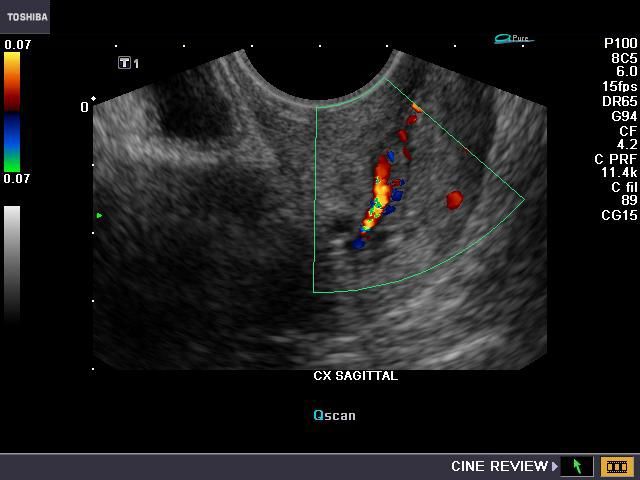

Case-2: Calcification in fibroid: (C- shaped calcific fibroid)

This intramural fibroid shows abundant calcification along the rim in a C-shape. Color Doppler image shows no significant vascular abnormality, except for some degree of "twinkling artefacts". Calcification of fibroids may occur as a peripheral ring or as popcorn type. Ultrasound image above is courtesy of Dr. Vikas Shukla, MD, India.